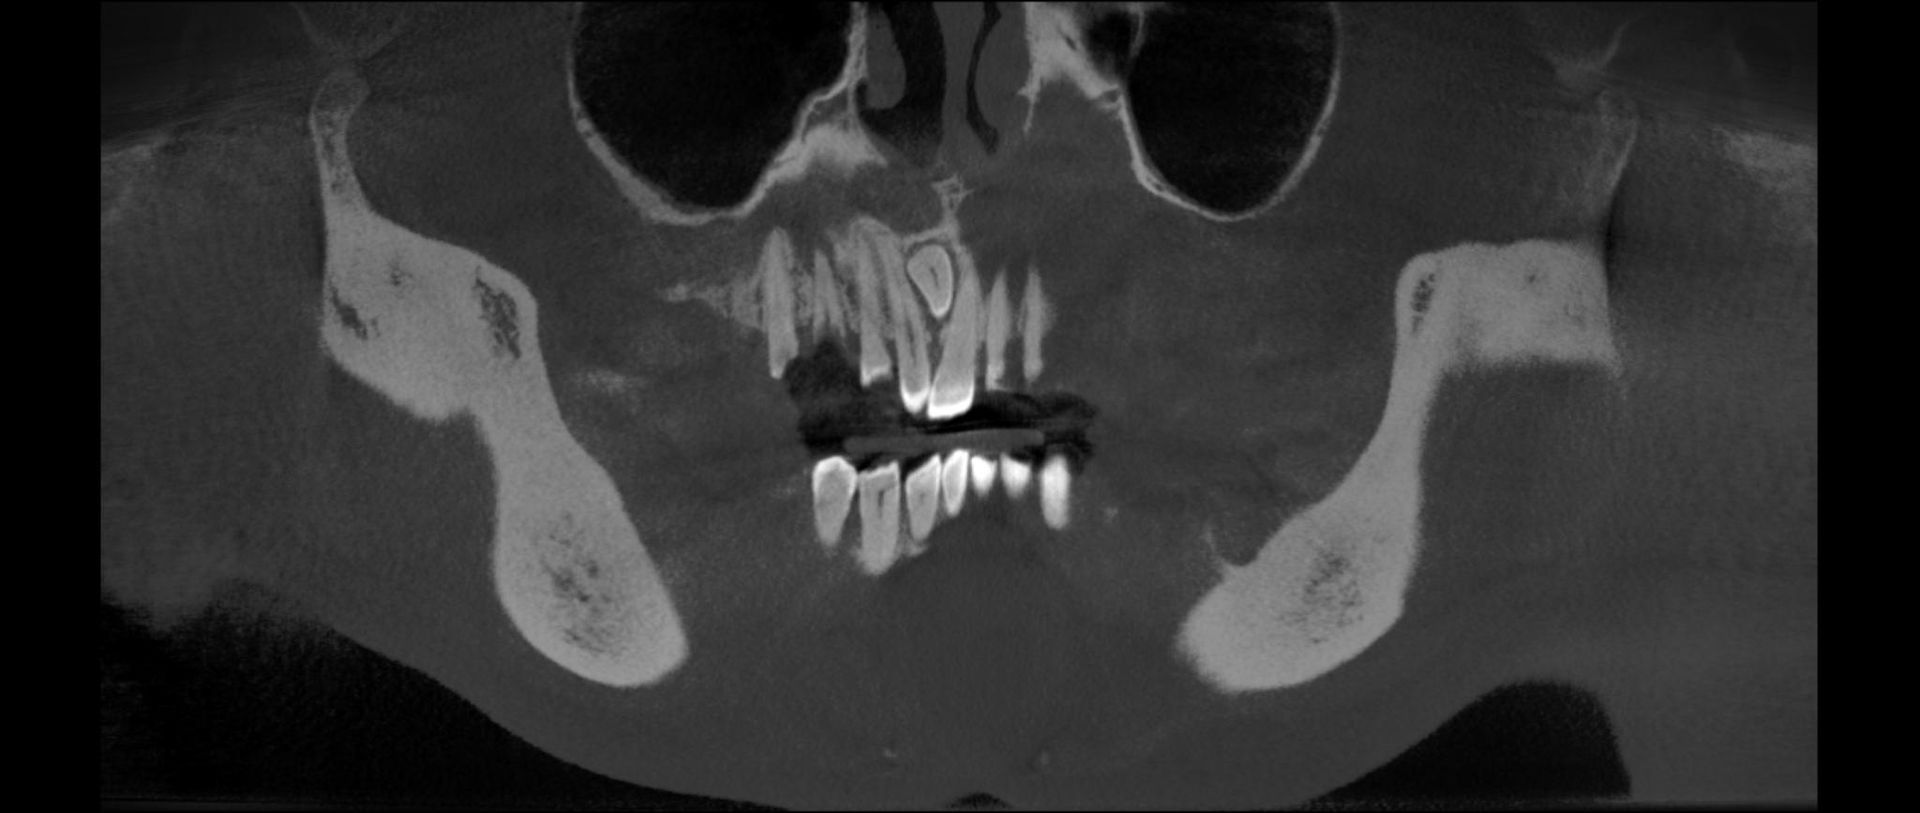

La funzione 3D, permette la visualizzazione completa delle strutture dentarie, ossee, in tre dimensioni, con ottima risoluzione di contrasto per lo studio dei tessuti molli.